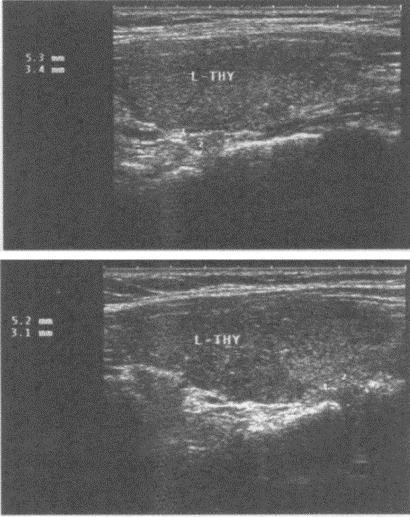

11、单项选择题

临床资料:男,49岁,常规体检。超声综合描述:甲状腺左叶上、下极后方可见大小均为0.5cm×0.3cm中等回声,边界清晰,形态规则,内回声均匀。

超声提示()。

A.甲状旁腺增生

B.甲状旁腺正常声像图

C.甲状腺旁肿大淋巴结

D.甲状旁腺腺瘤